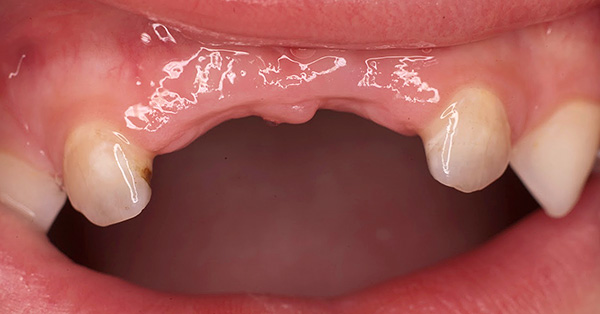

Às vezes, existe um conceito absolutamente errado dos pais de que, como os dentes de leite são temporários, você não precisa cuidar deles. Eles dizem que vão cair de qualquer maneira, e então já será possível fazer uma higiene mais completa. Com essa abordagem, a condição dos dentes do bebê em um bebê pode ser verdadeiramente catastrófica:

É importante entender que problemas na mordida do leite inevitavelmente terão um efeito prejudicial na mordida permanente e, às vezes (mesmo com processos inflamatórios graves), até os rudimentos de futuros dentes permanentes podem ser danificados.